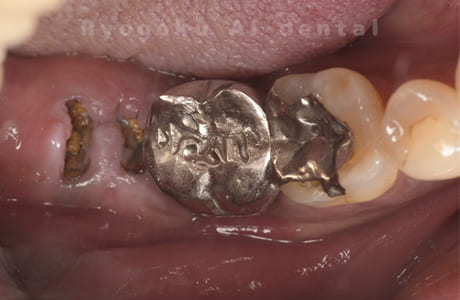

Case12

- 原因

- 左下7番歯牙破折

-

- 治療内容

- インプラント治療

- 治療費用

- 約600,000円

左下の奥歯が痛いとのことでご来院された患者様です。歯が完全に割れており、保存が不可能であったため、抜歯を行い、その際に骨に変わるお薬を入れ、十分な治癒を待ってからインプラント治療を行いました。経過良好で、大変満足されました。

<リスク・副作用>

治療後、痛みや違和感、出血、腫れなどが出る事があります。喫煙者、糖尿病などの方の場合、歯が生着しない場合があります。